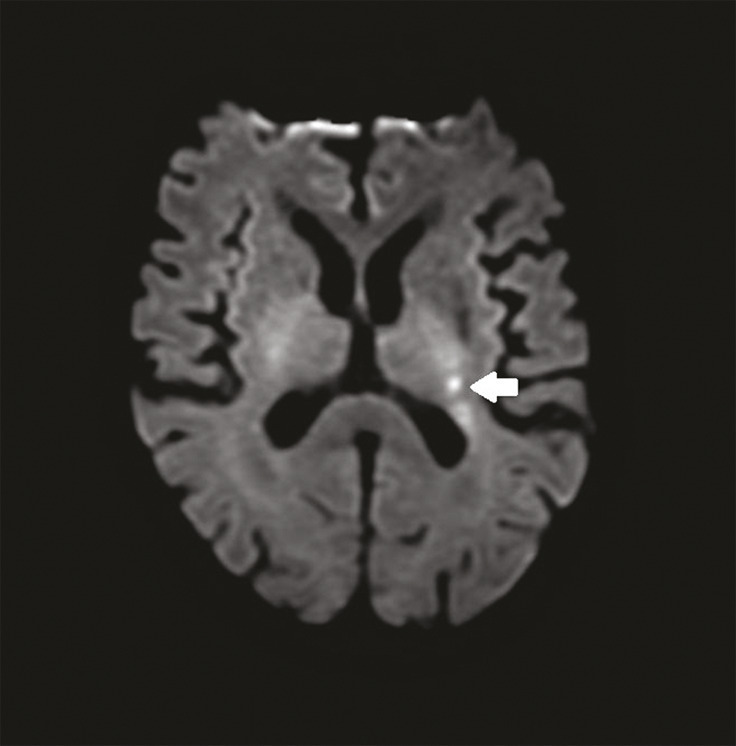

Cet homme de 71 ans est hospitalisé en mars 2020 pour un accident vasculaire cérébral ischémique (AVCi) de la capsule interne gauche (fig. 1 ) d’évolution favorable. L’enquête étiologique est négative mais des causes cardiovasculaires sont considérées comme probables. Après un épisode de céphalées intenses, mal calmées par le paracétamol, le patient est réhospitalisé en urgence début juillet pour une hémiplégie gauche ; l’imagerie révèle un aspect de vascularite cérébrale des gros troncs (fig. 2 ). La maladie de Horton est éliminée. Mi-juillet, un nouvel AVCi se traduit par une aggravation de l’hémiplégie gauche, une confusion mentale, une ataxie. Des échanges téléphoniques et écrits orientent alors vers le diagnostic de borréliose ; la ponction lombaire (95 % de lymphocytes, 8 hématies, protéinorachie 0,93 g/L, IgG anti Borrelia Burgdorferi > 240 UA/mL) et le profil sérologique de la maladie de Lyme (IgG 352 et IgM 2,3 UA/mL en faveur d’une infection semi-récente) confirment la neuro-borréliose active tardive (index de sécrétion intrathécale de 3,3 donc > 2) sous forme d’une méningo-vascularite.1 Un traitement par doxycycline est débuté puis le patient est pris en charge par un service de rééducation fonctionnelle dédié, avec d’importantes séquelles.